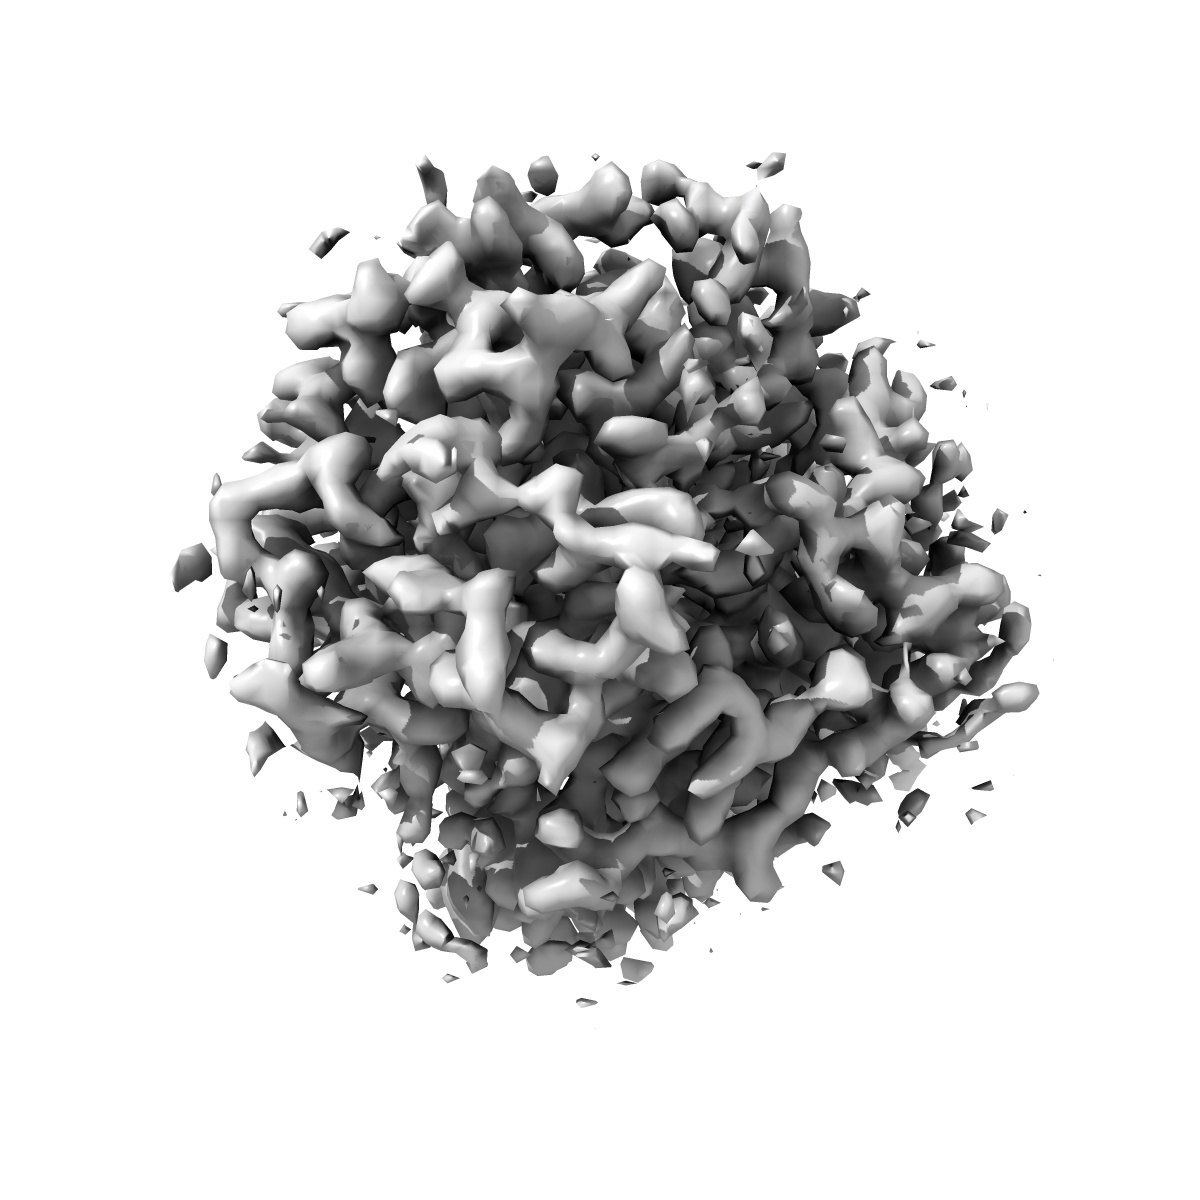

Cryo-EM structure of human norepinephrine transporter NET in the presence of dopamine in an inward-open state at resolution of 3.0 angstrom.

Single-particle3.0 Å

Fitted models: 8hfg

Molecular basis of human noradrenaline transporter reuptake and inhibition.

(2024) Nature , 632 , 921 - 929